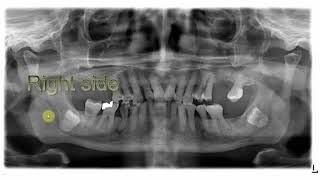

Radiographic Essment Of Third Molar Impacted...

Opg Signs Of Close 3Rd Molar Apex To Id C

Radiographic Essment Of Third Molars Wisdom Tooth...